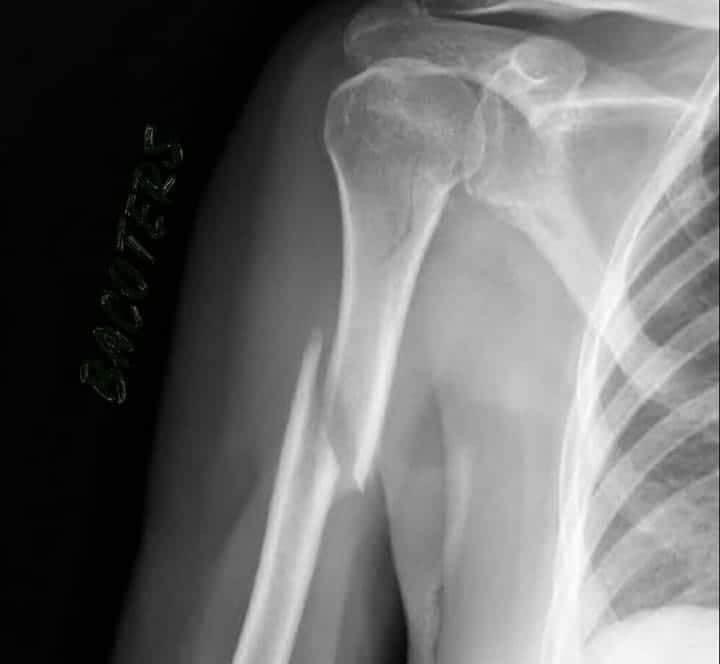

As for MM and his humerus fracture, this is very serious. This is what ended up Foggy's racing.

9. According to the MotoGP news, the fracture is partially displaced which I guess is better than a displaced fracture. Andy

14. Wow! Thats not a fracture....its a snap!